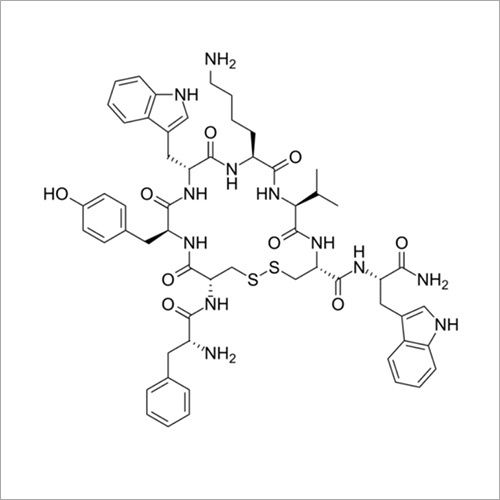

| रासायनिक नाम | Thymopentin |

| रासायनिक नाम | Thymopentin |